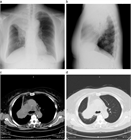

1. 無気肺とは肺組織が虚脱し、肺の含気が低下した状態である。

1. 閉塞性無気肺(腫瘍、粘液栓、異物、気管支結核など)と非閉塞性無気肺(炎症などによる肺実質の虚脱、受動性無気肺、円形無気肺など)に大別される。

1. 胸部X線撮影で無気肺が疑われたら、まずは胸部造影CTで鑑別をすすめ、必要に応じ喀痰培養、喀痰細胞診、気管支鏡などを行う。